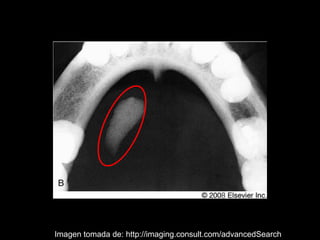

La sialolitiasis es la formación de obstrucciones mineralizadas en las glándulas salivales, causadas por el depósito de calcio y fósforo. Puede presentarse en las glándulas salivales mayores y menores, causando inflamación e hinchazón e incluso dolor durante las comidas. Los sialolitos se ven en radiografías como densidades radiopacas de varias formas y tamaños dentro de los conductos glandulares. El diagnóstico diferencial incluye otras imágenes radiopacas en los tejidos blandos.